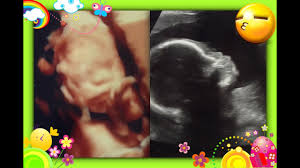

Bebe De 22 Semanas : 22 Semanas De Embarazo Embarazo Mes A Mes Pampers. Grávida de 22 semanas agora, todos os seus ossos contêm medula óssea que pode produzir glóbulos, e a sua pele armazena no seu interior finas capas de gordura corporal que são essenciais para o completo desenvolvimento do sistema nervoso. Final do 5º mês equivale aos dias: Sus ojos ya se han formado, pero los iris todavía no tienen color. La piel de tu bebé se verá arrugada hasta que tu pequeño gane más peso y llene sus pliegues. Desarrollo de tu bebé tu bebé esta semana se ve como un recién nacido, pero en miniatura.

Leia também sobre a nutrição e hábitos alimentares na gravide. Cómo son las 22 semanas de embarazo. La micro cámara viaja dentro del útero para mostrarnos imágenes espectaculares de los bebés con 22 semanas de gestación. Ya puede abrir y cerrar los ojos porque sus párpados ya se han formado. 22 semanas de embarazo ¡es capaz de sentir emociones!

El iris aún no ha adquirido su color, por lo que aún no está definido el color de los ojos del bebé. A las 22 semanas de embarazo la pancita está creciendo, pero aun puedes hacer tus actividades sin sentirte incomoda. Os olhos do bebê já estão desenvolvidos, mas ainda falta a pigmentação da íris. Desarrollo de tu bebé tu bebé esta semana se ve como un recién nacido, pero en miniatura. Ele pesa cerca de 430 gramas, e mede um pouco mais que 27. En esta primera tabla puedes comprobar la rápida evolución de tu bebé dentro de tu vientre en la primera etapa de embarazo. Mira cómo se desarrolla tu bebé a las 22 semanas de embarazo. 22 semanas de embarazo ¡es capaz de sentir emociones! 22.1 semanas, peso 499 gr. En esta semana, el feto pesa alrededor de 500 gr y mide unos 27 cm. Un bebé que nació prematuramente, cuando contaba con tan sólo 22 semanas de gestación, ha salido adelante y ya le han proporcionado el alta.en el momento de su alumbramiento el pequeño. Grávida de 22 semanas agora, todos os seus ossos contêm medula óssea que pode produzir glóbulos, e a sua pele armazena no seu interior finas capas de gordura corporal que são essenciais para o completo desenvolvimento do sistema nervoso. Bebê prematuro de 22 semanas luta pela sobrevivência 13/06/2017.

As páginas de desenvolvimento fetal têm o objetivo de dar apenas uma ideia geral de como o bebê cresce durante a gravidez. Desarrolo y evolución del bebé en el embarazo. 22.1 semanas, peso 499 gr. Sus ojos ya se han formado, pero los iris todavía no tienen color. Un bebé que nació prematuramente, cuando contaba con tan sólo 22 semanas de gestación, ha salido adelante y ya le han proporcionado el alta.en el momento de su alumbramiento el pequeño. Tamaño de texto más grande tamaño de texto grande tamaño de texto regular. Leia também sobre a nutrição e hábitos alimentares na gravide. Ya puede abrir y cerrar los ojos porque sus párpados ya se han formado. La piel de tu bebé se verá arrugada hasta que tu pequeño gane más peso y llene sus pliegues. Encuentra toda la información sobre la semana 22 de embarazo: Llegan a pesar sólo entre 400 y 500 gramos. Mira cómo se desarrolla tu bebé a las 22 semanas de embarazo. La micro cámara viaja dentro del útero para mostrarnos imágenes espectaculares de los bebés con 22 semanas de gestación.